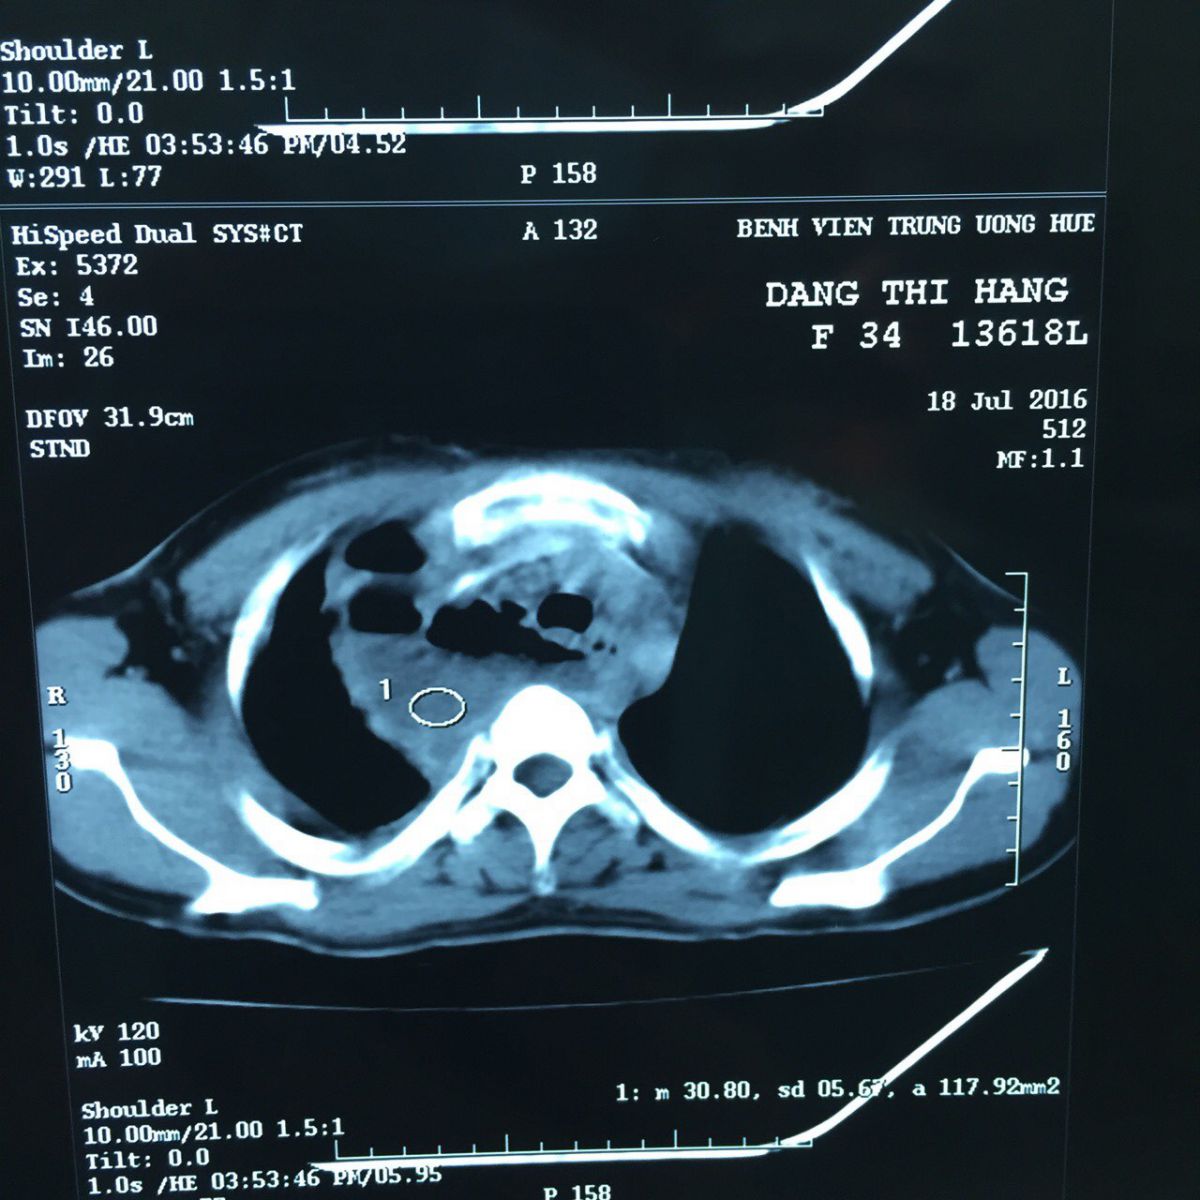

27/07/2016 14:36Cứu sống bệnh nhân bị áp xe trung thất do thủng thực quảnSáng 27/7, Bệnh viện Trung ương Huế cho biết, vừa phẫu thuật cứu sống bệnh nhân bị áp xe trung thất do thủng thực quản.